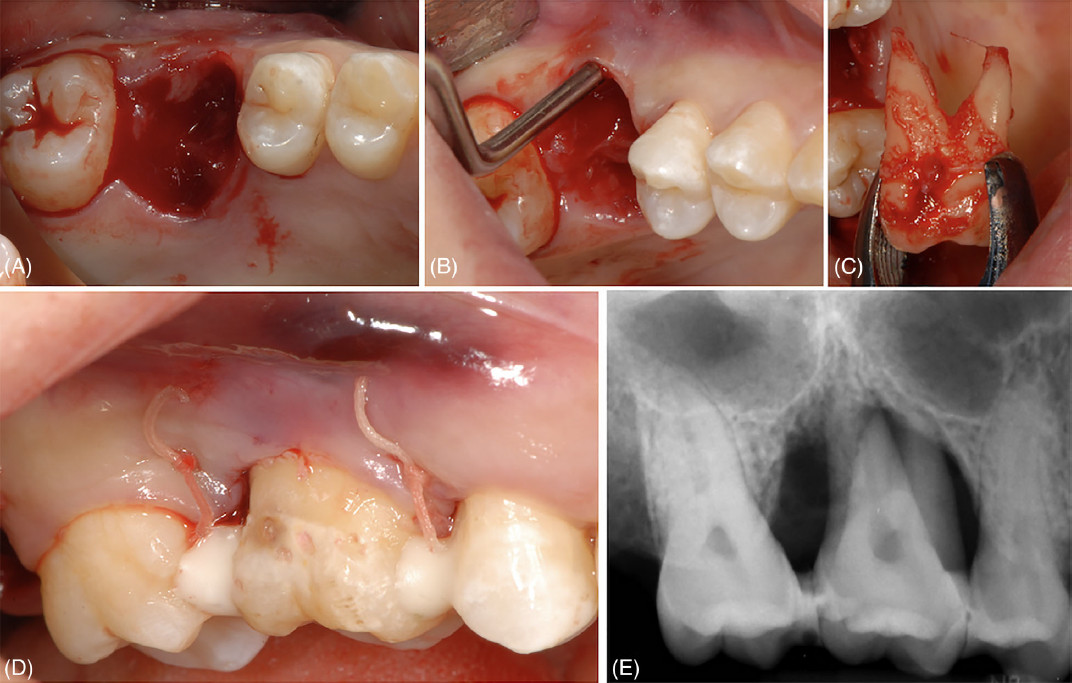

Фото 3. Удаление зуба 16 и его замещение с использованием зуба 18. (A) Лунка после удаления зуба 16. (B) Выраженная потеря костной ткани на щечной поверхности реципиентного участка. (C) Донорский зуб сразу после его удаления. (D) Клиническая картина сразу после операции и шинирования донорского зуба. (E) Рентгенологическая картина сразу после операции и шинирования донорского зуба

Фото 3. Удаление зуба 16 и его замещение с использованием зуба 18. (F) Клиническая картина через 24 месяца; зондирование показывает, что значительная часть щечного прикрепления, отсутствовавшая при первом визите, восстановилась. (G) Рентгенологическая картина через 24 месяца

Удаление зубов 16 и 18 также выполнялось щипцами; зуб 18 был немедленно трансплантирован в РУ с расположением его ЦЭГ на том же уровне, что и ЦЭГ соседних зубов, после чего был наложен шов.

В обоих случаях для стабилизации ДЗ применялось полужёсткое шинирование зуба (выполненное с использованием композитной смолы с ортодонтической проволокой или без неё), а все окклюзионные контакты были устранены алмазным бором.

При контрольном визите через 24 месяца подвижность и фуркационные поражения выявлены не были; значения глубины зондирования ≤ 4 мм были зафиксированы во всех точках обоих донорских зубов. Рентгенологических признаков резорбции корня, анкилоза или периапикальных/ периодонтальных очагов поражения обнаружено не было; уровень костной ткани у обоих донорских зубов составил более 50% длины корня.

В целом число карманов ≥4 мм уменьшилось с 32 до 4, FMBS составил 32%, а FMPS — 24%. Риск прогрессирования пародонтита, оценённый по методу PerioRisk, улучшился с категории «высокий риск» до «умеренно-высокий риск».